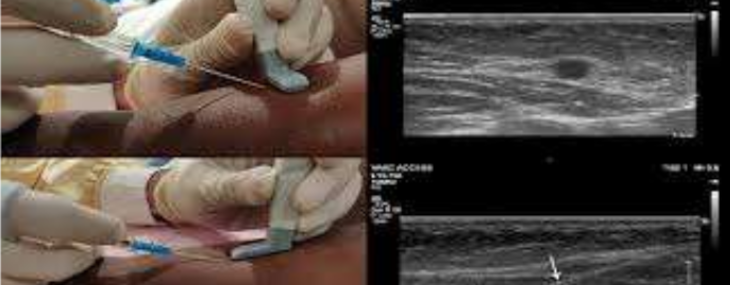

La UOC di Terapia Intensiva Pediatrica tratta i neonati a termine che presentano problematiche, i prematuri, i bambini e i pazienti cerebropatici fino ai 24 anni di età. Il corso si propone di trattare gli aspetti peculiari degli accessi venosi periferici e centrali nel paziente pediatrico ed adulto in emergenza/urgenza, con particolare attenzione alle novità circa le principali tecniche in uso, secondo le linee guida e la letteratura di supporto a livello nazionale. Il corso è suddiviso in una parte teorica e in una parte pratica in cui i partecipanti, suddivisi in piccoli gruppi, potranno esercitarsi su phantom e modelli anatomici animali con l'ausilio dell'ecografo per il posizionamento degli accessi venosi.